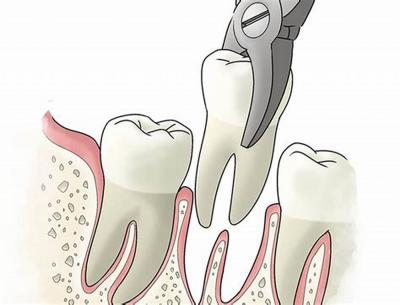

Процесс удаления коренного зуба

В некоторых случаях коренной зуб не поддаётся терапии и экстракция (удаление) – единственный вариант, который может предложить доктор.

Прежде чем приступить к удалению, врач делает рентгеновский снимок, чтобы определить точное расположение корней больного зуба.

Экстракция происходит следующим образом:

- хирург осуществляет расшатывание зуба, чтобы добиться необходимого расширения лунки;

- проводится отделение зуба от связок, удерживающих его в лунке;

- если зуб закреплён слишком прочно, удаление выполняют по частям, предварительно разрезав мягкие ткани;

- врач вынимает зуб и накладывает марлевый тампон в лунку, чтобы остановить кровотечение.

Фото 1. Для облегчения болезненных ощущений, если нет противопоказаний к компонентам, врач ставит инъекцию с обезболивающим препаратом.

Перед операцией врач вводит пациенту инъекцию с анестетическим (обезболивающим) препаратом. Это позволяет сделать процедуру абсолютно безболезненной.